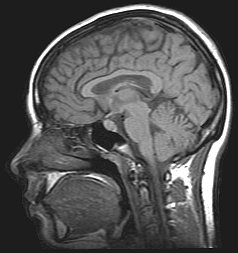

Aplicación en medicina

La resonancia magnética es una técnica que sirve para diagnosticar enfermedades mediante la obtención de imágenes del cuerpo. A pesar de que no existe efecto nocivo sobre el paciente, no se recomienda la práctica en embarazadas, salvo que su uso sea imprescindible.

La máquina que se utiliza en la resonancia magnética, debido a su dimensión y su tecnología, combina las ventajas de los equipos de alto campo magnético y los equipos abiertos. Así, se consigue una mayor definición y una mayor calidad en la imagen, y el paciente tiene una menor sensación de claustrofobia y además tiene una mayor comodidad. La duración de la prueba no depende de la gravedad de la afección, sino que depende de la región que se vaya a estudiar.[cita requerida]